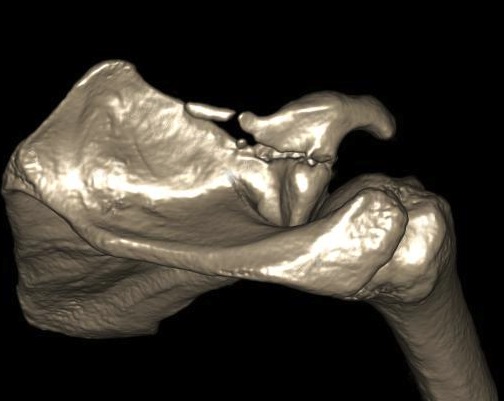

Combined Glenoid and Scapula Fractures

Case 1

- displaced glenoid fracture and neck fracture

- ORIF both through posterior / Judet approach